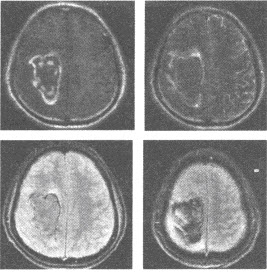

女,78岁,右侧肢体无力伴言语不清3天。查体:神志清,混合性失语,右唇沟浅,右肢体肌力1~2级,右侧巴氏征(+)。MRI扫描图像如下,最可能的诊断为()

A:脑梗死

B:脑出血

C:脑肿瘤

D:脑软化灶

E:脑内炎症